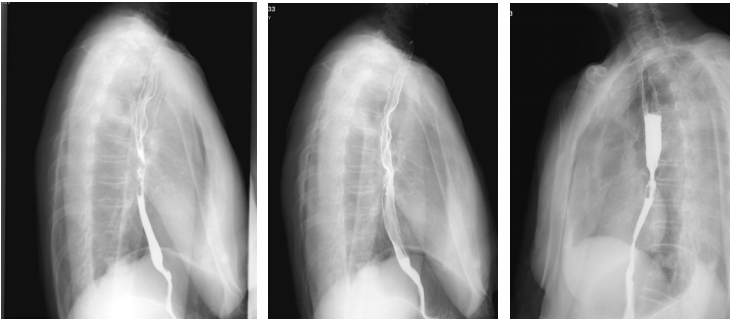

上消化道钡剂造影(2020-08-14):相当于胸7-9椎体水平的食道见范围长约35mm的狭窄段,管壁僵硬,粘膜皱襞破坏、中断,轮廓不光整,可见偏心性充盈缺损及小刺状龛影,狭窄段以上食管轻度扩张,对比剂排空延迟,余食道壁柔软,粘膜规则,未见充盈缺损及龛影,未见异常狭窄及扩张,贲门结构正常,开闭自如。

2021-01-15胃镜:距门齿26cm处食管局部黏膜苍白,见一纵行白色疤痕,局部无狭窄或新生物。

2022-03-22胃镜:食管新生物,慢性萎缩性胃炎伴胆汁反流。

最佳疗效评估:2022-10-13胃镜:进镜至食管中段距门齿30cm处环形狭窄,所见食管上段黏膜充血水肿。